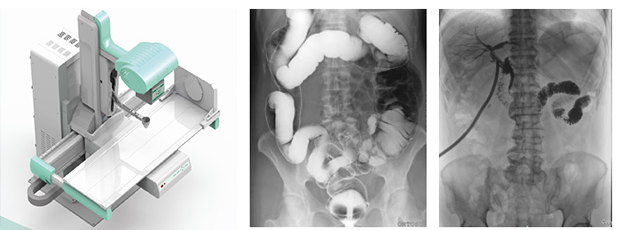

動態(tài)DR是一款多功能DR,能夠數(shù)字拍片、數(shù)字透視、數(shù)字造影。

動態(tài)DR具有大幅面(17inch×17inch)高清拍片、大幅面(17inch×17inch)透視、視頻實時保存回放、可視化造影、毫秒級點片等基礎(chǔ)功能,以及斷層融合、數(shù)字減影等延展性功能。

普愛醫(yī)療作為全球較好的數(shù)字影像設(shè)備供應(yīng)商,專注于DR系列產(chǎn)品的技術(shù)創(chuàng)新,在全國范圍內(nèi)率先推出動態(tài)DR。以其“一機(jī)多用”集常規(guī)拍片、胃腸、透視、造影于一體的多功能作用深受放射科臨床醫(yī)生的鐘意。

普愛醫(yī)療的動態(tài)DR擁有滿足各類臨床應(yīng)用的多種功能、高品質(zhì)的影像后處理系統(tǒng),動態(tài)CCD探測器的核心技術(shù)更方便實現(xiàn)技術(shù)升級,對醫(yī)院提高診療水平和診療效率、降低設(shè)備重復(fù)購買成本具有重要作用,是功能強(qiáng)大、性能優(yōu)異的一款高端數(shù)字設(shè)備。如果您想購買普愛醫(yī)療的動態(tài)DR,或想了解產(chǎn)品具體技術(shù)參數(shù),歡迎聯(lián)系我們。